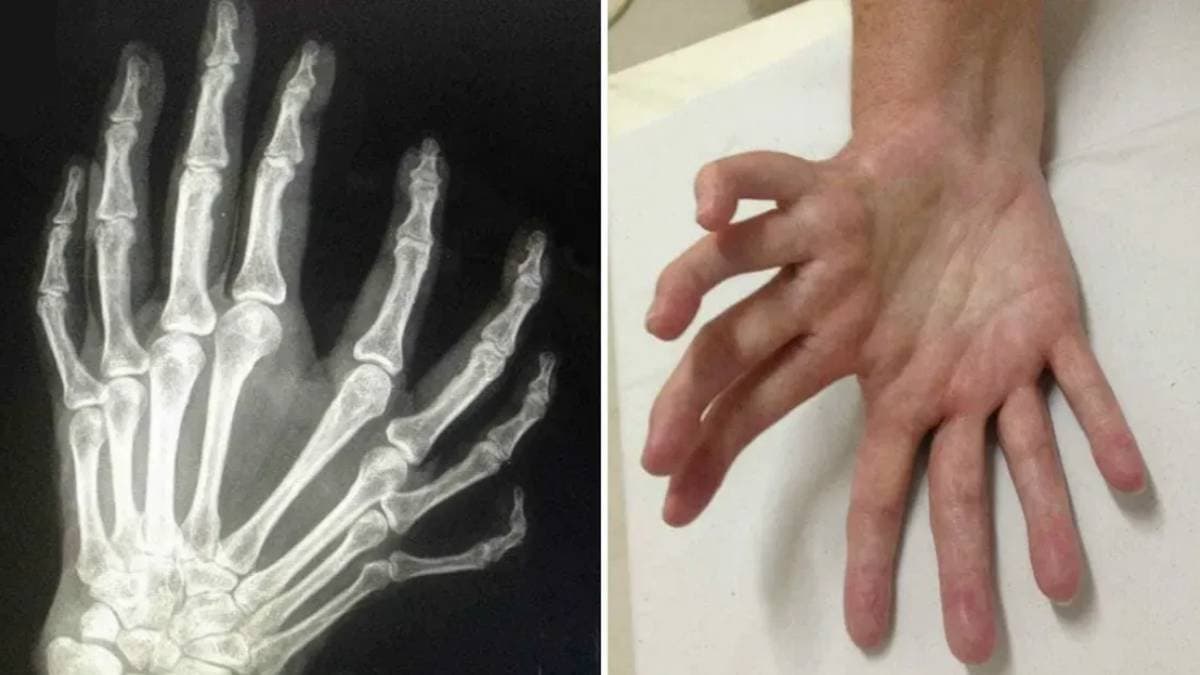

রোগটির প্রচলিত নাম, ‘মিরর হ্যান্ড সিন্ড্রোম’। চিকিৎসাবিজ্ঞানের ভাষায় একে বলা হয়, ‘আলনার ডিমেলিয়া’। প্রকৃতপক্ষে এটি একটি অত্যন্ত বিরল জন্মগত ত্রুটি। এই বিশেষ শারীরিক অবস্থায় রোগীর হাতে কোনও বুড়ো আঙুল থাকে না। তার পরিবর্তে সাত বা আটটি আঙুল তৈরি হয়, যা দেখতে অনেকটা মাকড়সার পায়ের মতো। অনেক সময় হাতের দু’দিকে সমান আঙুল থাকে জলে সেগুলিকে পরস্পরের প্রতিবিম্বের মতোও লাগে। সেকারনেই একে মিরর হ্যান্ড সিন্ড্রোম বলে।

কেন এই রোগ হয়, সেটা নিয়ে নিশ্চিত নন বিজ্ঞানীরা। তবে সাধারণ ভাবে মনে করা হয়, এর প্রধান কারণ জিনগত অস্বাভাবিকতা। সাধারণত এই সিন্ড্রোমের ফলে শুধু আঙুলের সংখ্যাই বেশি হয় না, বাহুর গঠনেও ত্রুটি দেখা যায়। বর্তমানে এর চিকিৎসা মূলত সার্জারির উপর নির্ভরশীল। পলিসাইজেশন নামক একটি জটিল অস্ত্রোপচারের মাধ্যমে আক্রান্ত হাতের একটি অতিরিক্ত আঙুলকে সরিয়ে বুড়ো আঙুলের জায়গায় আনা হয়। যায় রোগী কোনও কিছু আঁকড়ে ধরতে ও সূক্ষ্ম কাজ করতে সক্ষম হন। আর এর পাশাপাশি, অপ্রয়োজনীয় আঙুলগুলিকে কেটে বাদ দেওয়া হয়। সঠিক চিকিৎসা, সার্জারি এবং ফিজিওথেরাপির মাধ্যমে অধিকাংশ রোগীই স্বাভাবিক জীবনযাপন করতে পারেন।